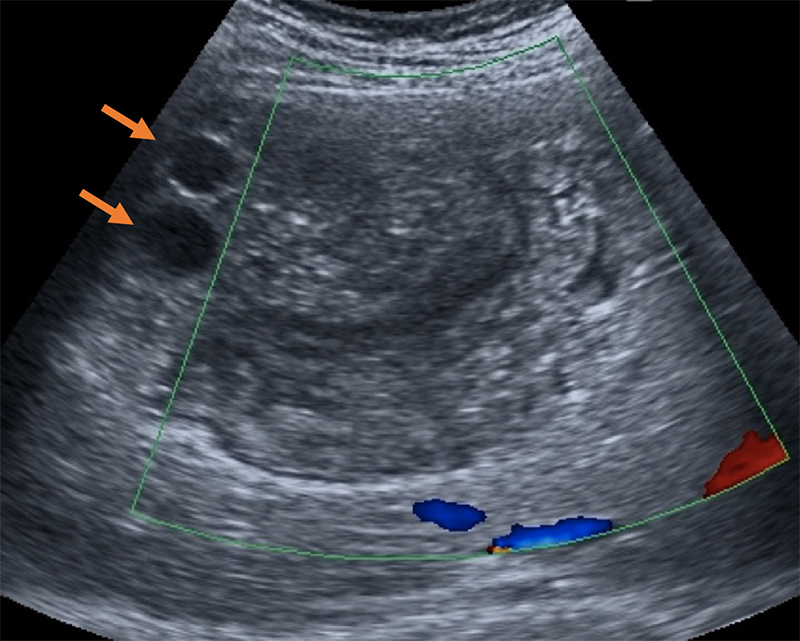

Figure 54A. Transverse views of the liver revealing moderate periportal fibrosis. Note the thickened hyperechoic walls surrounding the portal vein and branches.

Figure 54B. Transverse views of the liver revealing moderate periportal fibrosis. Note the thickened hyperechoic walls surrounding the portal vein and branches.